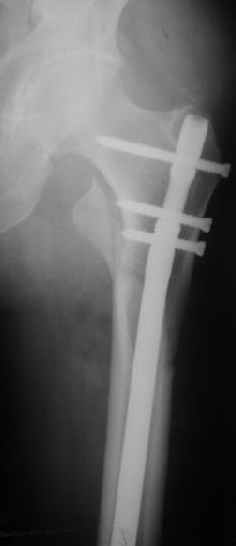

В частности, на проксимальном конце сделано еще одно дополнительное статическое отверстие. Можно ввести в проксимальном отделе 4 винта, из них 3 статические (2 в круглые отверстия и 1 по нижнему краю овального). Картинки в приложении. На дистальном конце стержня тоже кое-что улучшено. Спрашивайте в аптеках, как говорится. Выпускается предприятием "ЦИТО" (Москва), то есть это малобюджетное решение.

Конечно, мы не синтезируем остеопорозые вертельные переломы согласно прилагаемому примеру, винты 6 мм вырежутся. Но у более молодых при хорошем качестве кости такие или подобные гвозди с поперечным расположением винтов вполне применимы для меж- и подвертельных переломов.

Картинка красивая, но на мой взгляд, не совсем оптимальная: Слишком медиально введён стержень - риск аваскулярного некроза головки бедра.

Это было года 2,5 назад, мы тогда еще уточняли возможности шинирования с угловой стабильностью гвоздем с поперечным расположением винтов при переломах проксимального отдела бедра. Пациенту не пришлось приобретать намного более дорогой рекон или проксимальный гвоздь. В приложении еще несколько примеров применения того гвоздя при высоких переломах бедра, в том числе с более латеральной точкой входа. Гвоздь изгибаем для этого.